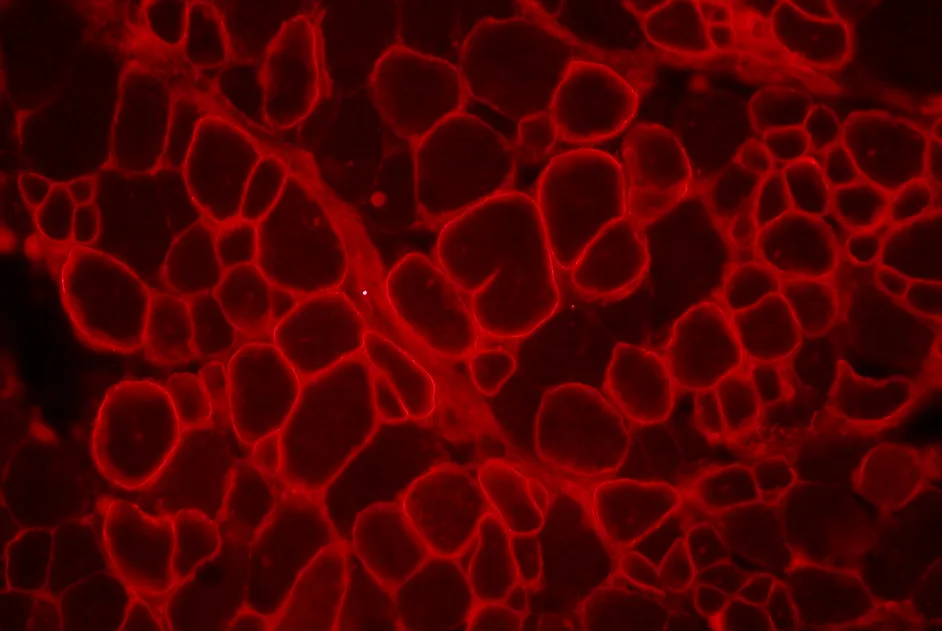

Efficacité du saut de l’exon 45 par des snARN U1 dans des cultures de myoblastes humains atteints de dystrophie musculaire de Duchenne.